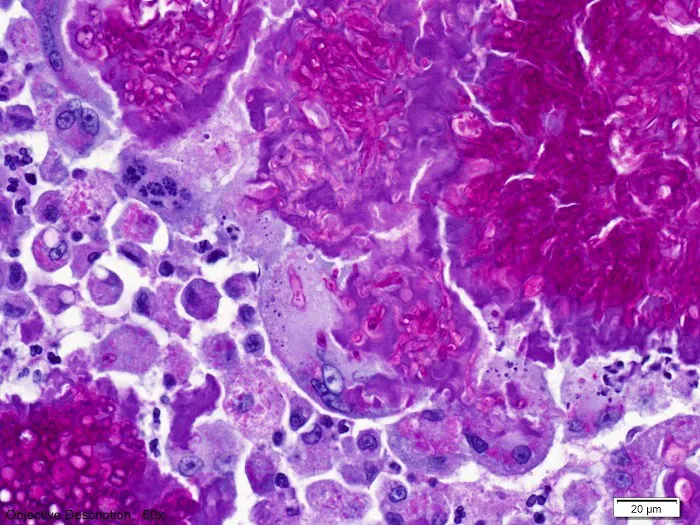

- **Dermatopathology (Skin Biopsy):** A key specialization providing highly accurate interpretations of veterinary skin biopsy specimens, essential for complicated dermatology and allergy cases.

- **Histopathology (Biopsy):** The microscopic examination of tissue sections (biopsies) for definitive diagnosis, including tumor identification and complex inflammatory diseases.

- **Cytology:** The examination of cells (collected via fine needle aspirates, smears, etc.) to aid in rapid diagnosis of masses and inflammatory conditions.

- **Specialized Dermatopathology Expertise:** The company possesses a unique and advanced specialization in skin pathology, which is crucial for solving frustrating and difficult-to-diagnose dermatology cases.

Specializing in dermatopathology, the team provides expertise in interpreting skin biopsies, which is essential for diagnosing the often frustrating and difficult skin conditions common in pets. This specialized focus has earned the trust of local veterinarians, with one stating, "Not going anywhere else for my dermatology cases in the future." The service has been instrumental in helping clinics "move forward" with complex cases like pemphigus, providing the "incredible support and helpful answers" that lead to successful treatment plans.